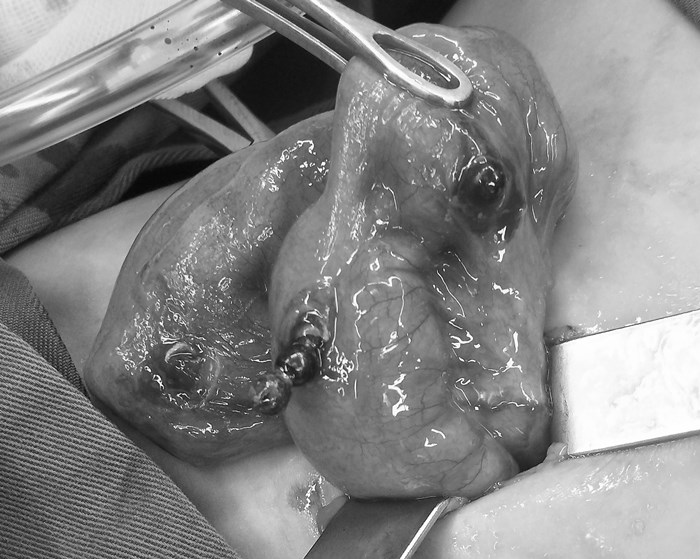

入院時(shí),小舒舒精神萎靡,腹脹明顯,出現(xiàn)了腸梗阻癥狀。胃腸小兒外科醫(yī)生鄭臨海會(huì)診后,立即為小舒舒開具X光片檢查,檢查發(fā)現(xiàn)在消化道內(nèi)的11顆珠子已經(jīng)排成一只“手鐲”,小舒舒的腸壁及腸子被“吸”成了一團(tuán)。

小舒舒立即被收治住院,經(jīng)充分評(píng)估,胃腸小兒外科在麻醉科協(xié)助下,為小舒舒行小腸異物取出+修補(bǔ)術(shù)。

術(shù)中發(fā)現(xiàn),小舒舒幾處腸道已經(jīng)出現(xiàn)了穿孔破裂的情況,若不將磁力珠取出,可能會(huì)危及生命。經(jīng)過(guò)一個(gè)小時(shí),小舒舒腸道里的磁力珠被順利取出。